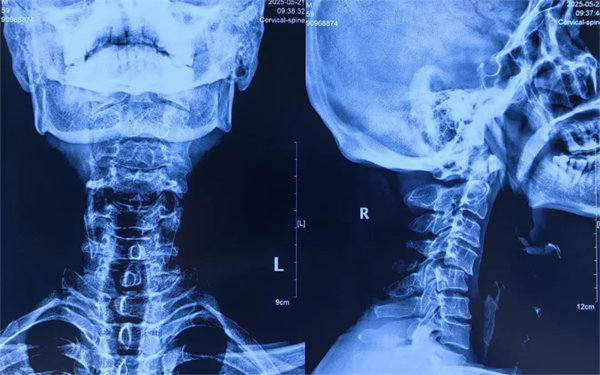

術(shù)前

患者受傷后曾在外院接受保守治療,但肢體麻木癥狀持續(xù)存在。轉(zhuǎn)入我院時,頸椎CT及MRI顯示:頸4/5椎骨折脫位,脊髓受壓明顯,若不手術(shù)治療,可能面臨永久性神經(jīng)功能障礙。我院骨四科團(tuán)隊(duì),制定了前路ACDF手術(shù)方案:通過頸前側(cè)入路,切開復(fù)位、切除椎間盤,解除脊髓壓迫,同時植入融合器、鈦板固定,重建頸椎正常序列及穩(wěn)定性。術(shù)后患者麻木感消失,復(fù)查顯示頸椎序列恢復(fù)良好,目前已康復(fù)出院。